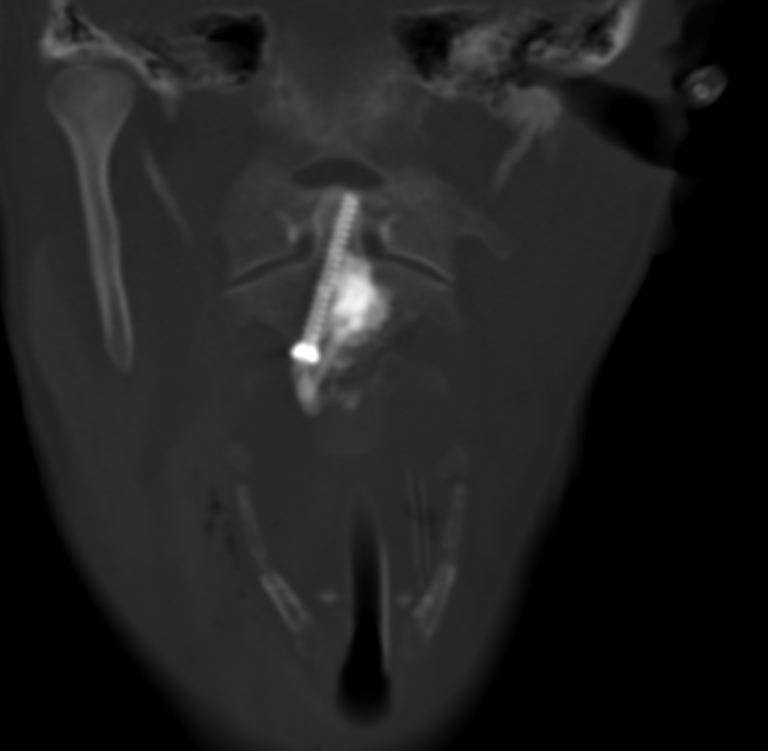

Consolider pour redonner de l’autonomie : une ostéosynthèse mini-invasive de la dent de la vertèbre C2

L’équipe de radiologie interventionnelle du CHU de Clermont-Ferrand a réalisé une première en Auvergne : une ostéosynthèse percutanée de la dent de C2 chez une patiente atteinte de cancer, présentant une lésion osseuse à haut risque de fracture.

L’intervention se déroule en salle de radiologie interventionnelle, sous anesthésie générale. Grâce à un guidage scanner et scopique en continu, une précision millimétrique est assurée à chaque étape :

• Hydrodissection cervicale : injection de sérum physiologique pour écarter les structures à risque (artère carotide, veine jugulaire, trachée).

• Mise en place de la vis : introduction d’un trocart osseux, puis d’une broche et enfin d’une vis canulée adaptée à l’anatomie du patient.

• Cimentoplastie complémentaire : injection de ciment acrylique dans la lésion pour renforcer la consolidation et la stabilité de la vis.